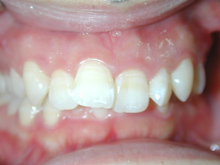

S.T様は下顎前歯の叢生が主訴でお母様と無料矯正相談で来院されました。

口を閉じる際に口元の緊張があり、横顔に突出感がありました。

以前に上顎前歯の部分矯正をされたご経験があるとお話しされておりました。

そのためか上顎犬歯の横幅(幅径)が通常より少なく思いました。

試料採取より診断の結果、上顎の前歯にも軽度の叢生があり、口元の緊張を改善し、

前歯の叢生の治療のために抜歯が必要であることを説明し、了承が得られたので本格矯正で治療をすすめることとなりました。

上顎前歯に軽度の叢生、下顎前歯に叢生がみられます前歯の上下の接触状態が緊密でなく軽度の舌癖の存在を疑います。

臼歯部は1歯 対 2歯で咬んでいます。

各ステージで順調に治療がすすみました。

治療は順調に進みました。

犬歯の幅径が狭い事の対応として犬歯にダイレクトボンディングを行う、

下顎前歯のストリッピングを行うなどのプランを考えましたがその両方とも行うことなく動的治療を完了しました。

舌癖の存在は後戻りの大きな原因となりますので今後の保定治療でも注意が必要で、引き続き舌癖の改善を行います。